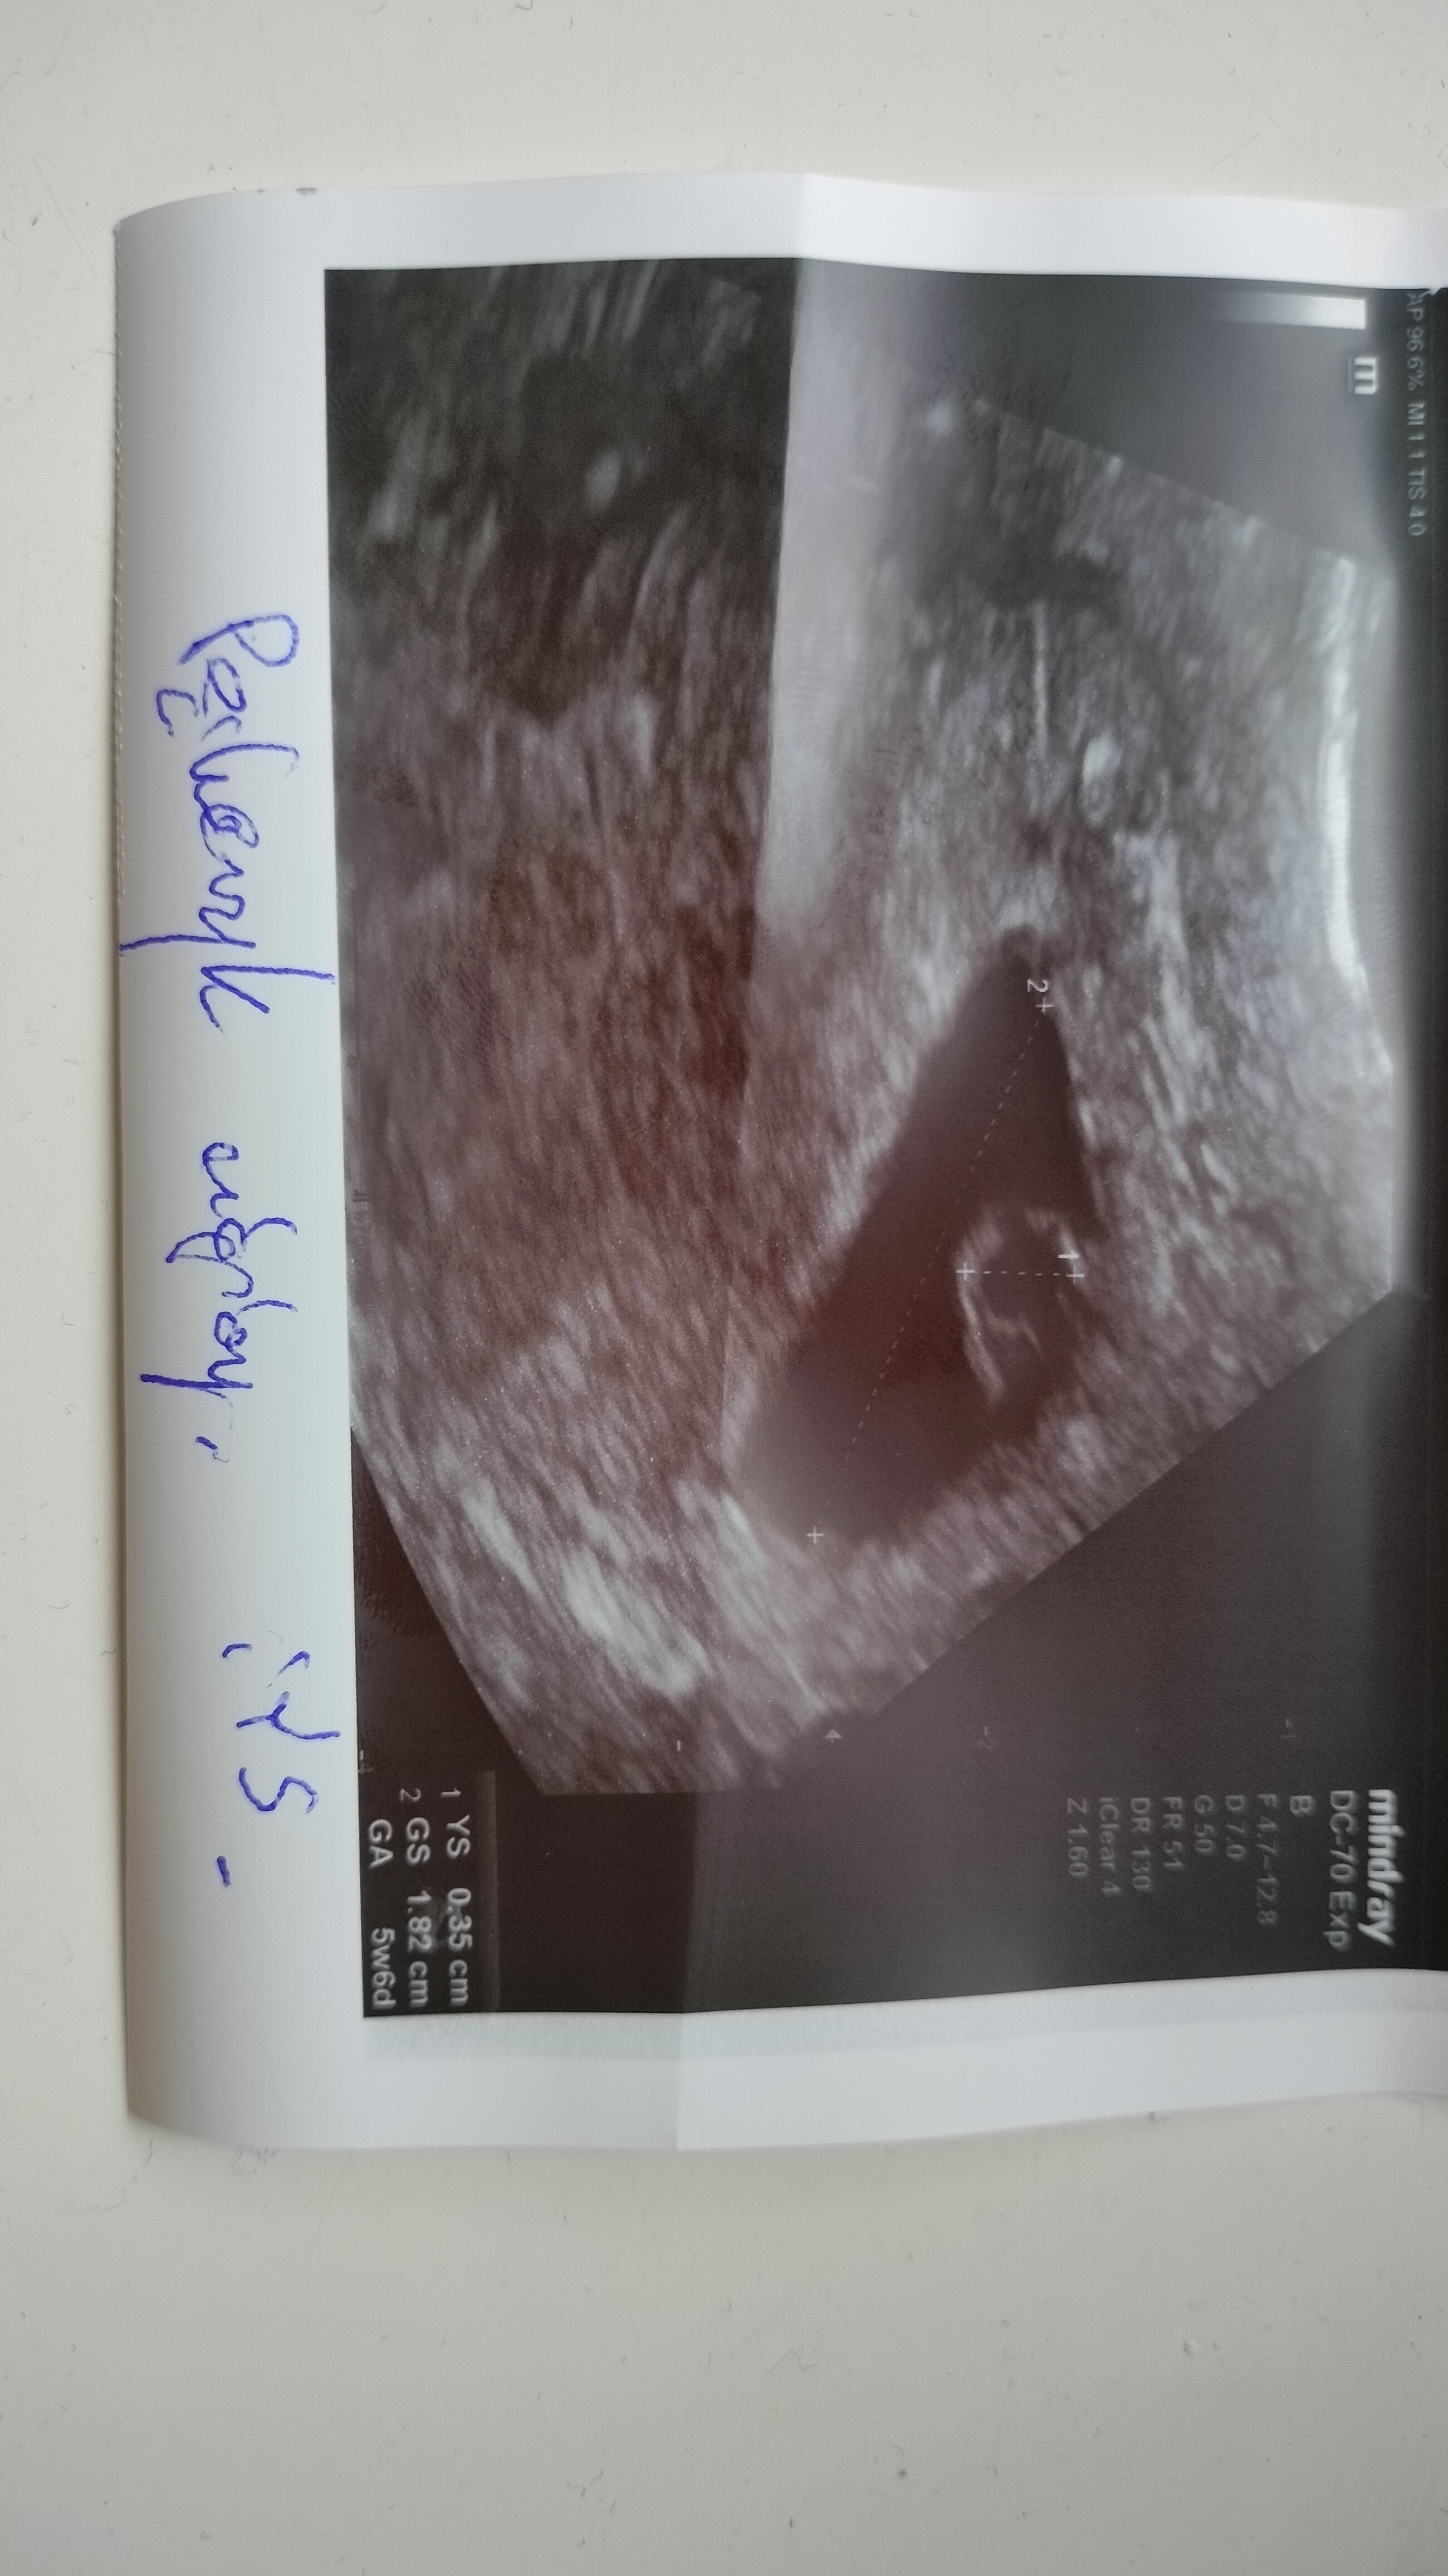

Cześć dziewczyny. Mam mętlik w głowie i szukam porady. Miałam USG w piątek 12 maja na IP bo miałam plamienie które okazało się być od acardu ale mniejsza z tym, był pęcherzyk 6,9 mm i ciałko żółte 1,8 mm, dzisiaj tj. 18 maj miałam znów USG, pęcherzyk 18,2 mm, ciałko żółte 3,5mm, lekarz mówi że jest przygotowane miejsce na zarodek ale jeszcze go nie widać i na pewno pojawi się w ciągu 2 lub 3 dni i mam powtórzyć USG za tydzień. Okres miałam 2 kwietnia z tym że to nie był prawdziwy okres tylko w trakcie brania duphastonu pojawiło się krwawienie mimo że nie powinno go być. Później już nie miałam. I teraz się zastanawiam czy nie jest przypadkiem juz za późno na zagnieżdżenie zarodka? Wydaje mi się że skoro w piątek był pęcherzyk i ciałko żółte to już po tych 6 dniach powinien być zarodek a tu nic. Co myślicie, martwi mnie to mimo że lekarz nie wydawał się zaniepokojony. Biorę duphaston w razie komplikacji. To moja pierwsza ciąża i strasznie się boje i dlatego tyle pytań w mojej głowie się rodzi

• IMG20230518122334.jpg

1,7 MB · Wyświetleń: 674